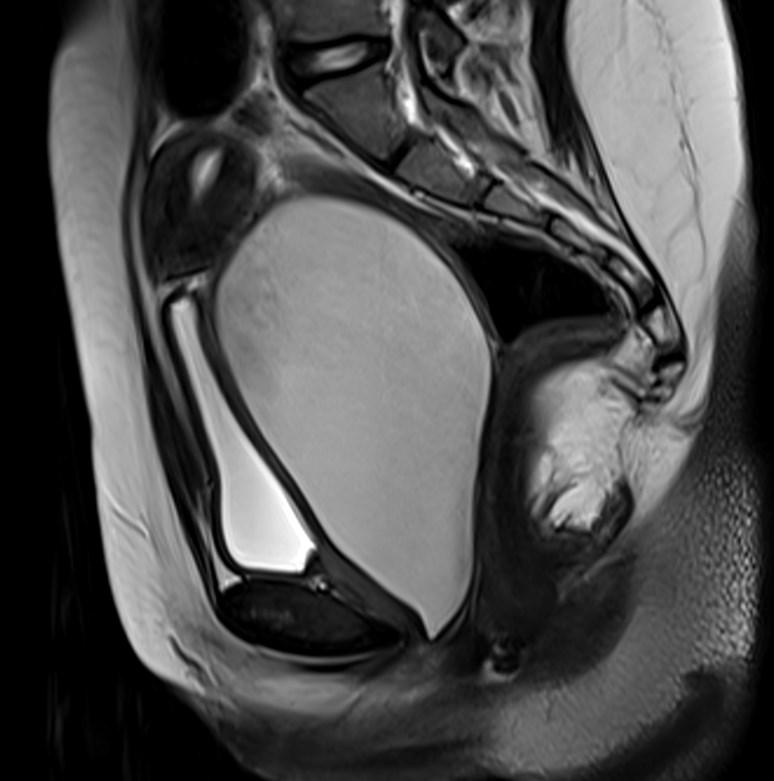

MR images showed hemorrhagic fluid in a distended vagina. The uterine cavity is not dilated.

In haematocolpos, there is accumulation of menstrual blood in the vagina in the setting of an anatomical obstruction, usually an imperforate hymen. When there is concurrent uterine distention, the term haematometrocolpos is used.